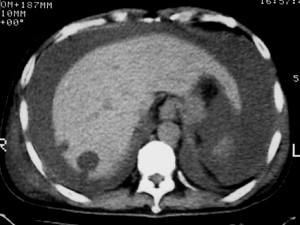

m ,60岁,右上肺ca术后一月。

右侧肺癌术后:肝内可见多个大小不等的低密度结节影。腹腔及双侧胸腔大量积液。考虑:肺癌并胸膜及肝脏转移。

腹水,肝及右肾多发低密度影。考虑转移。

肝及右肾转移瘤,双侧胸水

右肾及肝内多发转移瘤,胸水。

1、右肺癌术后改变。2、双侧胸水、腹水。3、多发性肝囊肿,右侧肾囊肿。

目前转移或复发的依据不足,术后才一个月,个人认为还是让临床去判断,而且需结合术前常规检查,有无肝肾囊肿;另外有一个疑问:肝胃间隙内团状软组织影是胃食管交接区吗,胃腔太小了吧,有无手术史请楼主告知.